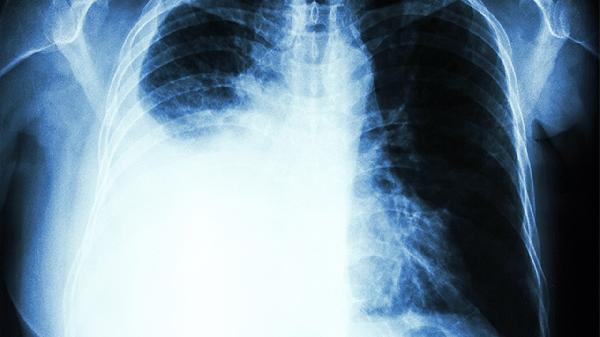

肺气泡破裂时,气体进入胸膜腔刺激神经,患者常感到患侧胸部尖锐刺痛,疼痛可能随呼吸或咳嗽加重。部分患者描述为“撕裂样”疼痛,需与心绞痛鉴别。胸痛程度与破裂范围相关,少量气胸可能仅轻微不适。

由于破裂肺组织失去通气功能,患者会出现不同程度的呼吸急促。轻者仅在活动时气促,重者静息状态下即感窒息。伴随血氧饱和度下降时,可能出现口唇发绀、烦躁不安等缺氧表现。

大量气胸会导致纵隔移位压迫心脏,出现血压下降、心率增快等休克表现。患者可能面色苍白、四肢湿冷,需紧急处理以防呼吸循环衰竭。